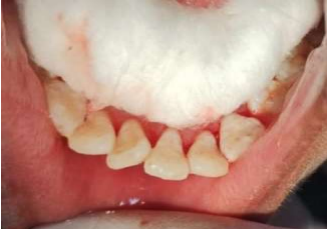

Figure 1 a, Figure 1b

Lingual aspects of the teeth were spot etched using 37% phosphoric acid gel for 30 seconds (VISTA VIS- 502115 Best-Etch Dentsply), rinsed off with air-water spray for 10 seconds and then air-dried. A thin layer of bonding agent (Prime & Bond NT Dentsply) was applied on the etched surfaces as per the manufacturer’s instructions. The splint was secured with light curing resin composite (Spectrum Dentsply) with 30 seconds of photopolymerization (Figure 1a). Once the splinting with composite and wire was performed, the patient was counselled and an intraoral periapical radiograph was taken to evaluate the tooth repositioning . The splint was evaluated for its stability, mobility, premature contact and comfort to the patient. The patient was given antibiotics (Amoxicillin 500 mg for every eight hours a day for seven days and Metronidazole 400 mg for every eight hours a day for seven days) to prevent infection as chance of spread of infection due to higher vascularization. The analgesics (Ibuprofen 400 mg every eight hours a day for three days) was given to reduce pain and decrease inflammation for improving healing with 0.2% chlorhexidine gluconate rinse every 12 hours for 14 days as an antiplaque mouth rinse. Postoperative written instructions for the consumption of a soft diet, maintenance of regular oral hygiene, avoidance of direct trauma by mastication, oral habits and immature contact were given. The patient was recalled after one week and examined for the stability of the splint. Splint was

placed for four weeks with weekly evaluation. At end of four weeks, splint was removed (Figure 1 b) with diamond bur. After one year of continuous three months follow up, the patient referred in the Endodontics for further treatment. At two years of follow up, color, contour, position of gingiva was excellent, well maintained alveolar bone height (Figure 2) & the patient was completely satisfied with result obtained.